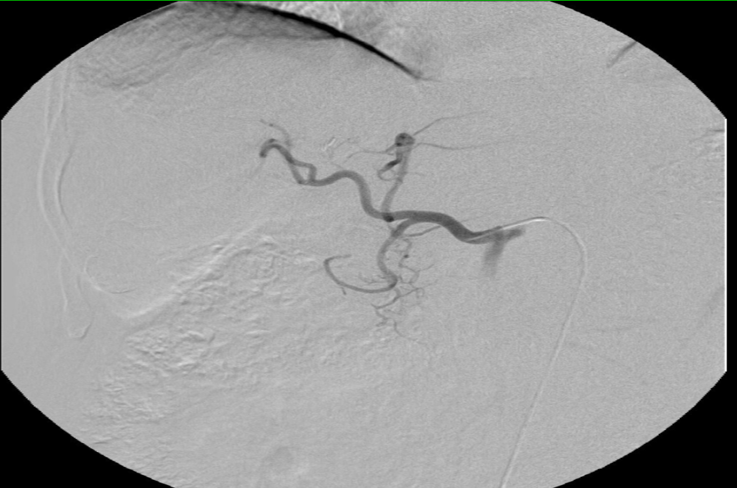

肝动脉化疗栓塞(2018-07-20)

造影显示:肝脏外科术后,灌注洛铂栓塞超液化碘油+洛铂的混合乳剂,未见明显碘油沉积、肿瘤染色灶。

影像学检查、TACE未提示肿瘤复发,患者出院后服用中药调理。